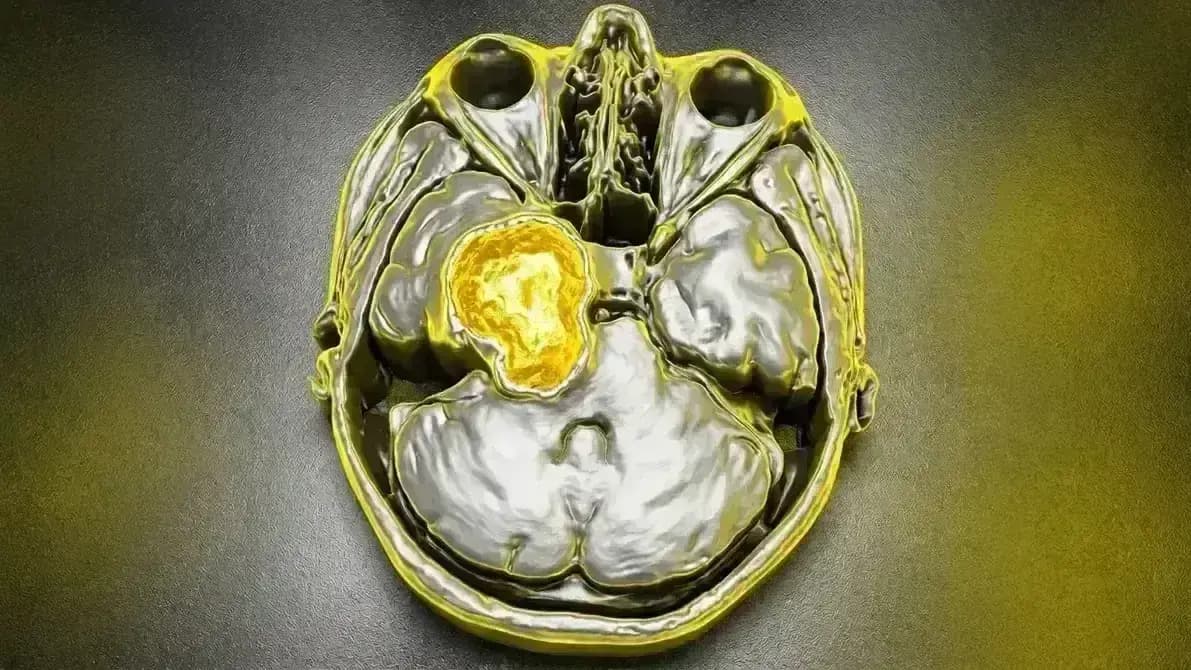

Tumor benigno (Grau I) que nasce das células de Schwann do nervo trigêmeo (V par craniano). Pode crescer na fossa média (perto da têmpora) ou no ângulo ponto-cerebelar (perto do ouvido). Diferente da neuralgia do trigêmeo clássica, aqui há perda de sensibilidade e possível fraqueza muscular.

- 📊 RM com contraste (diagnóstico diferencial com meningioma)